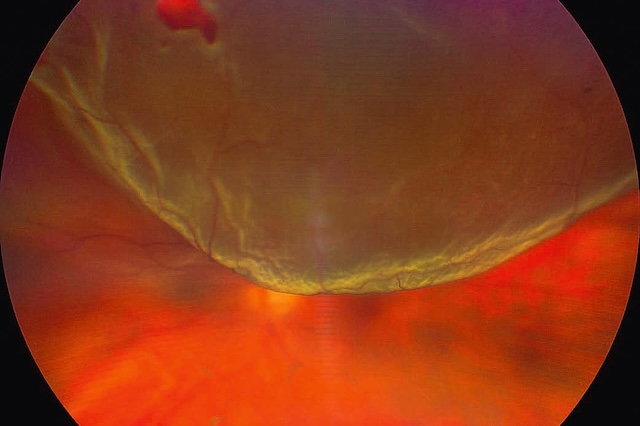

Image ultra grand champ prise par rétinographie couleur avec système Zeiss Clarus, illustrant un décollement de rétine supérieur de type bulleux au niveau de l’œil gauche. La rétine, habituellement plaquée contre la paroi interne du globe oculaire, apparaît ici soulevée en nappe ondulée, formant une bulle translucide flottant dans le champ supérieur de l’image. Ce soulèvement net, aux contours bien délimités, est typique d’un décollement rhegmatogène, secondaire à une petite déchirure rétinienne localisée en supérieur, invisible ici mais responsable du passage du liquide sous-rétinien. Le pôle inférieur de la rétine reste partiellement en place, permettant de mieux apprécier le contraste entre la zone décollée, plus terne et floue, et la zone encore attachée, plus rouge et bien vascularisée. Une petite hémorragie flotte dans le vitré supérieur gauche, signe d’un traumatisme ou d’une traction antérieure. Cette vue capture avec précision la dynamique d’un décollement en phase évolutive.

Cette image spectaculaire en fond d’œil ultra-grand champ met en lumière un décollement de rétine total de l’œil gauche, capté grâce à un système d’imagerie de haute définition, ici probablement un Zeiss Clarus. Au centre de l’image, une vaste déchirure rétinienne occupe la région supérieure, précisément autour de la position horaire de midi, laissant s’échapper le fluide sous-rétinien qui sépare la rétine sensorielle de l’épithélium pigmentaire. Le relief sinueux et bombé de la rétine décollée, flottante, donne un effet de voile ondulé, accentué par les nuances vert-jaune et les variations de réflectivité. L’organisation en plis radiaires et la texture en vagues immobiles soulignent la tension mécanique exercée par la traction vitréo-rétinienne à l’origine de la déchirure. Ce type de document visuel est essentiel non seulement pour le diagnostic et le suivi post-intervention mais aussi pour comprendre l’étendue de la lésion avant une chirurgie de rétinopexie ou de vitrectomie. Ce cliché relève d’une imagerie rétinienne spécialisée, typiquement utilisée en rétinopathie chirurgicale.